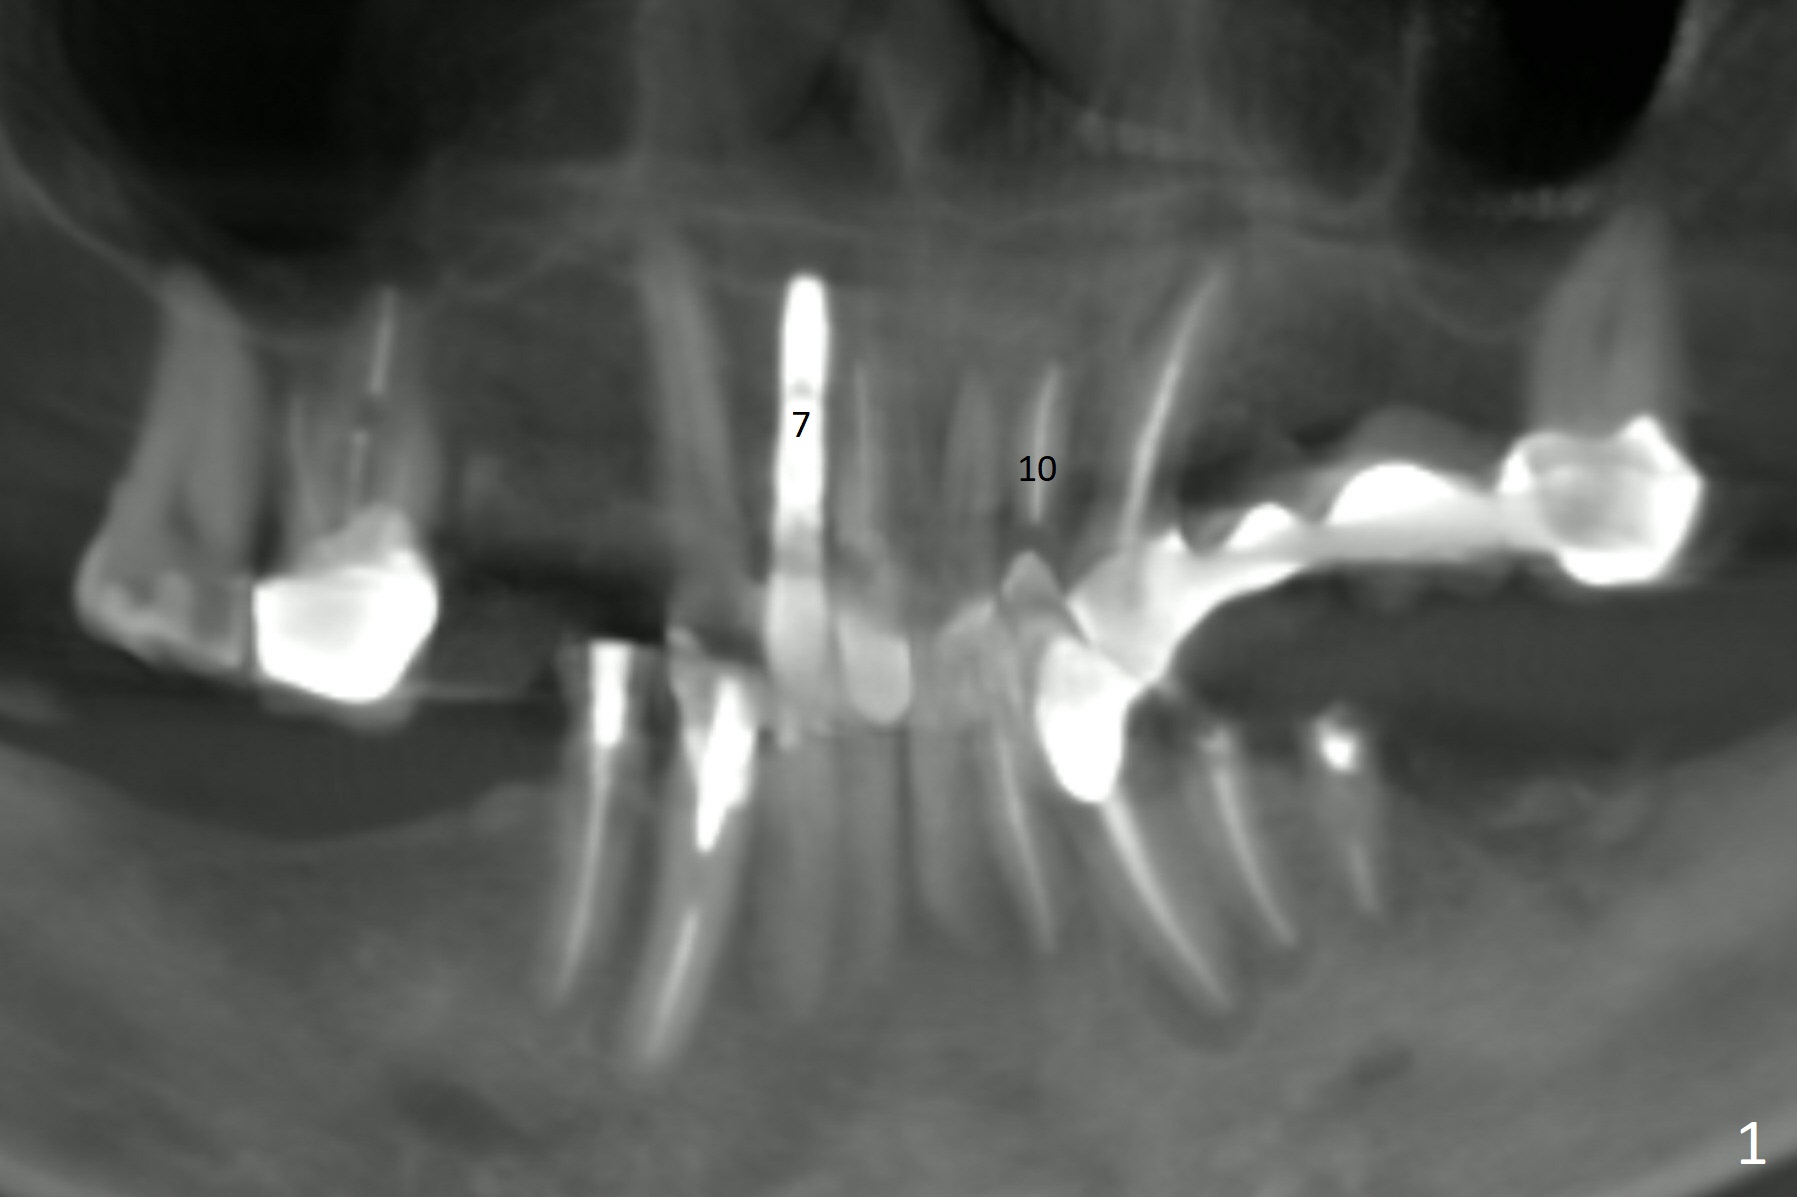

Thin Buccal Plate and Alveolus of Lateral Incisor

A 60-year-old man fractures the tooth #10 after implant at #7 (Fig.1). An implant should be placed in the middle of the socket at #10 since there is periapical radiolucencey at #9 and 11 (Fig.2 CBCT). The buccal plate at #10 is thin (Fig.4). A 3.8x15 mm implant (the smallest 2-piece) appears to be large for the alveolus (Fig.5). The gingiva must be thin as well. This is called thin biotype. In fact the buccal plate seems to have undergone bone resorption post 3.8x15 mm implant placement at #7. Therefore a 2.5 or 3x14 or 16 mm 1-piece implant will be placed at #10 (Fig.5). Also prepare angled ones. Take photos of #7 and 10 to show bone resorption and the thin gingiva. If the caries is not extensive, perform socket shield. In fact a 1-piece implant is chosen because of the narrow mesiodistal space.